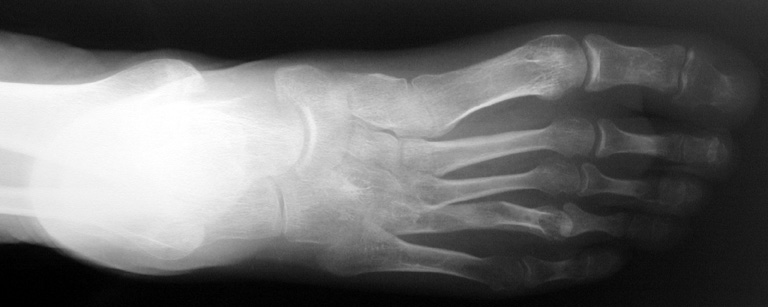

El parmağı (metakarp) ve ayak parmağı (metatars) kısalıkları doğuştan tek başına, geniş bir sendrom grubuyla birlikte, travma sonrası, Freiberg hastalığı (avasküler nekroz) sonrası görülebilir.

Doğuştan metakarp ve metatars kısalığının görülme sıklığı 1/1000’den azdır. Kadınlarda erkeklere göre 5 kat daha fazla görülür ve sıklıkla (%72) iki taraflıdır. En sık 4. parmak tutulur. Bu tür olgularda sorunun nedeni tam olarak bilinmemekle brlikte deformitenin genellikle epifiz plağının erken kapanmasından kaynaklandığı düşünülmektedir.

Metakarp kısalığında kozmetik görünümün bozulması ve dominant elin kullanımı sırasında yorulma, metatars kısalığında ise kozmetik haricinde metatarsalji, kısa parmağın dorsale kayması sonucu deformite oluşması, plantar yönde açılanması sonucu ağrı ve bası ülserleri, ve ayakkabı giymede zorluk nedeniyle ameliyat gerekebilir.